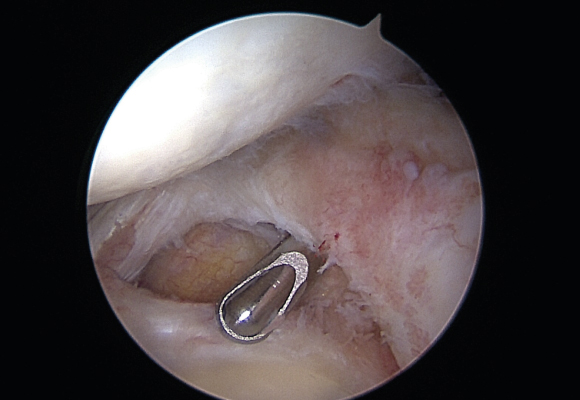

연골판봉합술

혈관이 있는 부위에 파열이 발생한 경우 연골판을 봉합해 주는 수술 시행

ㆍ환자 동의를 받은 자료이며, 이미지 사진은 실물과 다를 수 있습니다. (22.06.09)